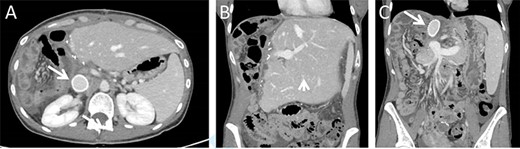

Histologic images of the resected lesion including IVC segment. (A) H&E staining, X20 magnification, demonstrating cells showing cytological atypia with areas of necrosis (arrow). (B + C) H&E staining, X20 magnifications, showing the tumour adjacent and originating from the IVC.

Macroscopic examination of the resected specimen observed a 1.92 kg liver lesion, measured 11x15x23cm. Attached blood vessels could not be separated from said lesion. Histologic examination revealed the diagnosis of a high grade leiomyosarcoma, with wide areas of necrosis, focally prominent cytological atypia and mitotic activity. Immunostains were diffusely positive for Calponin, Desmin, SMA and negative for Myogenin, CD34, S100, CAM5.2 and AE1/AE3. The tumour originates from a large venous type blood vessel – The IVC (Fig. 4). Inked resection margins were free of tumour.